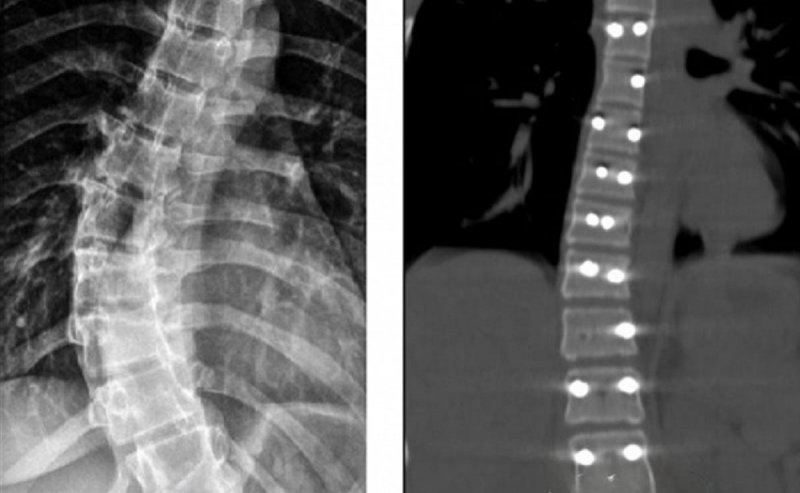

На этот раз медицинская помощь потребовалась 14-летней пациентке, страдающей идиопатическим сколиозом. У нее было диагностировано искривление позвоночника под углом в 40 градусов. Такая деформация со временем могла негативно сказаться на функционировании сердца и легких. Медики приняли решение о проведении операции с целью остановить прогрессирование заболевания и вернуть позвоночнику правильное положение.

В ходе оперативного вмешательства девочке была установлена прочная металлическая конструкция, обеспечивающая фиксацию позвоночника в выпрямленном положении. После операции пациентка быстро восстановилась и была выписана из больницы.